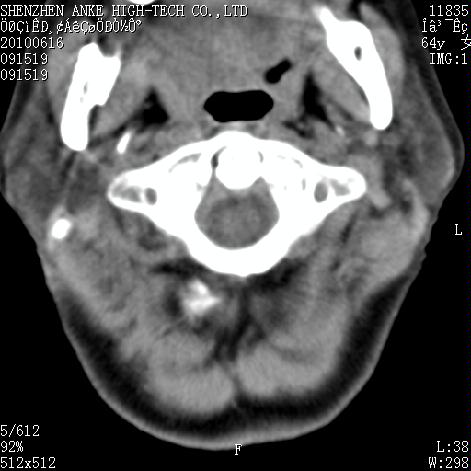

标题: CT27132:患者女,64岁,颈部及全身多处包块,现觉吞咽困难4 [打印本页]

标题: CT27132:患者女,64岁,颈部及全身多处包块,现觉吞咽困难4

右侧甲状腺占位,肿瘤可能性大,癌

右侧甲状腺癌伴右颌下腺淋巴结转移

右侧甲状腺癌伴淋巴结转移

右侧甲状腺癌伴淋巴结转移可能性大

右侧甲状腺癌伴淋巴结转移可能性大。

右侧甲状腺癌伴右颌下腺淋巴结转移!建议增强!